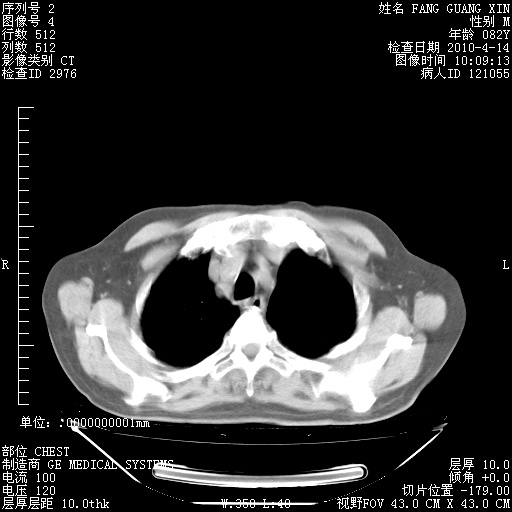

肺部CT平扫未见异常。